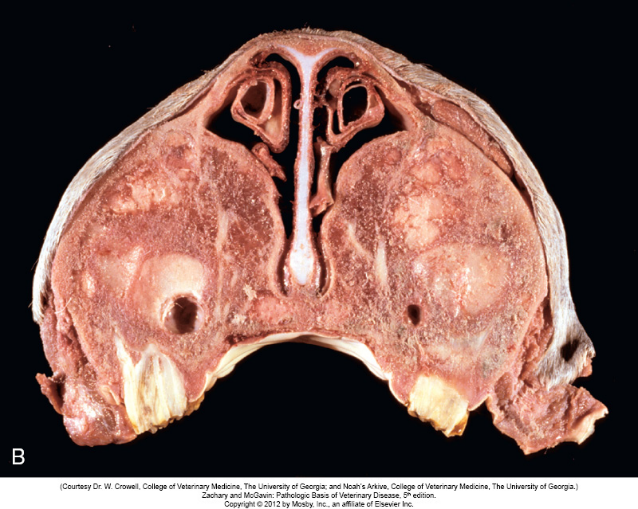

Diagnose: kæbeaktinomykose. PAD: kronisk deformerende pyogranulomatøs osteomyelitis. Histopatologisk diagnose: aktinomykose.

Karaktersitisk: Mandiblen er kraftigt forstørret, bindevæv, knoglevæv og pus

Patogenese: betændelse i mundhulen (oftest beskadiget tand) og herefter lymfogen spredning.

Ætiologi: Actinomyces bovis